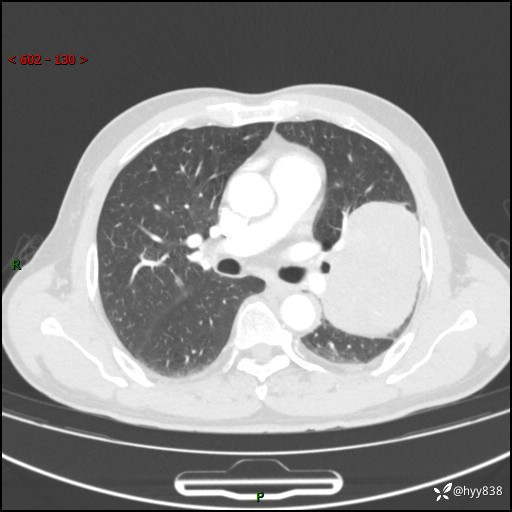

68岁/男,发现左下肺占位5天。如此大的肿块,患者竟然没有症状---结果公布~

【患者信息】:68岁/男

【主诉】:检查发现左下肺占位5天。

【现病史及既往史】:患者于4天前外院行“经尿道钬激光碎石术”,住院期间胸部CT检查发现左下肺肿块,患者平素无明显咳嗽咳痰,无心慌、胸闷、胸痛、呼吸困难、低热、盗汗,无头痛、头晕,无腹痛、腹胀等不适,现患者为求进一步治疗,遂来我院就诊,以“左下肺肿块”收入我科。 患者自起病以来,精神可,睡眠可,饮食可,大小便正常,体重无明显改变。

【检查】:胸部CT增强扫描